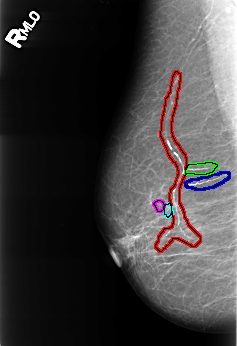

B_3244_1.RIGHT_MLO

FILE: B_3244_1.RIGHT_MLO.OVERLAY

TOTAL_ABNORMALITIES 5

ABNORMALITY 1

LESION_TYPE CALCIFICATION TYPE VASCULAR DISTRIBUTION N/A

ASSESSMENT 2

SUBTLETY 4

PATHOLOGY BENIGN_WITHOUT_CALLBACK

ABNORMALITY 2

TOTAL_OUTLINES 1

ABNORMALITY 3

ABNORMALITY 4

LESION_TYPE CALCIFICATION TYPE FINE_LINEAR_BRANCHING DISTRIBUTION N/A

ABNORMALITY 5